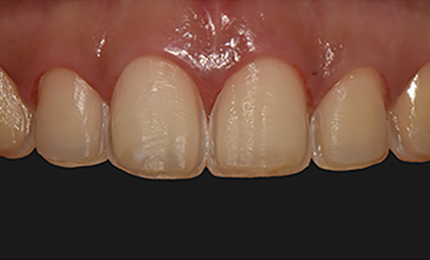

서울바른훈치과 라미네이트 전후 사례

• 시술전

무삭제 or 최대 0.1mm 폴리싱

시술 후